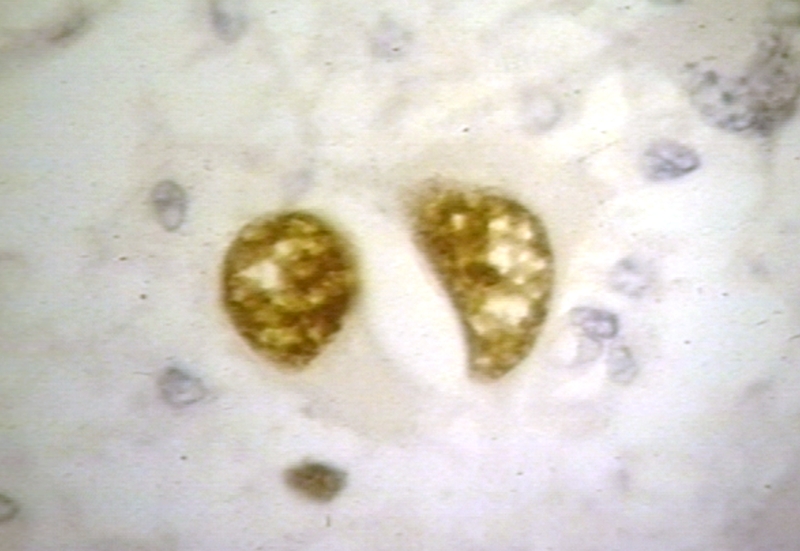

HISTOLOGY: NERVOUS: BRAIN: PROGRESSIVE MULTIFOCAL LEUKOENCEPHALOPATHY, PML; IMMUNOPEROXIDASE